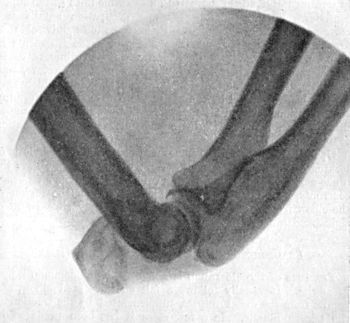

| 36. | Backward Dislocation of Elbow in a Boy | 89 |

| 37. | Bony Outgrowth in relation to insertion of Brachialis Muscle | 90 |

| 38. | Radiogram of Incomplete Backward Dislocation of Elbow | 91 |